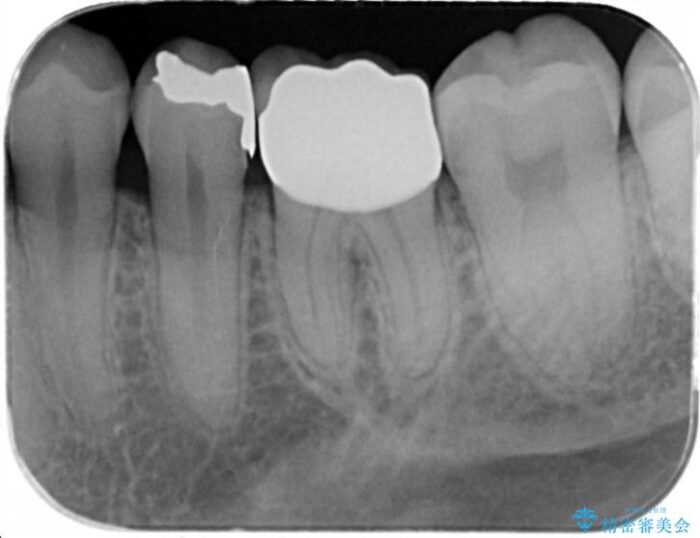

銀歯の適合や形態不良により、食べ物が非常に挟まりやすく、虫歯の再発も銀歯の下に認められる状態でした。

不適合な修復物、虫歯の除去を丁寧におこなったのち、清掃しやすい形態へと回復する精密なセラミック治療を行います。